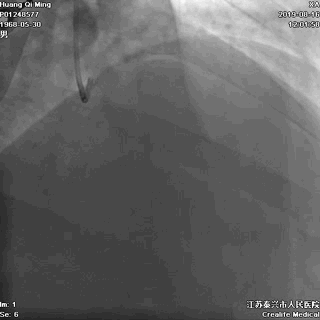

LCX PCI过程

手术器械:

7F EBU3.5

0.014” Runthrough NS

2.0*20 Maverick 球囊

2.75*23 DES

2.75*12 Quantum Maverick 球囊

3.0*8 Quantum Maverick 球囊

导丝通过病变

球囊扩张,PTCA

支架定位和植入

高压扩张使支架贴壁

LCX植入后即刻效果满意